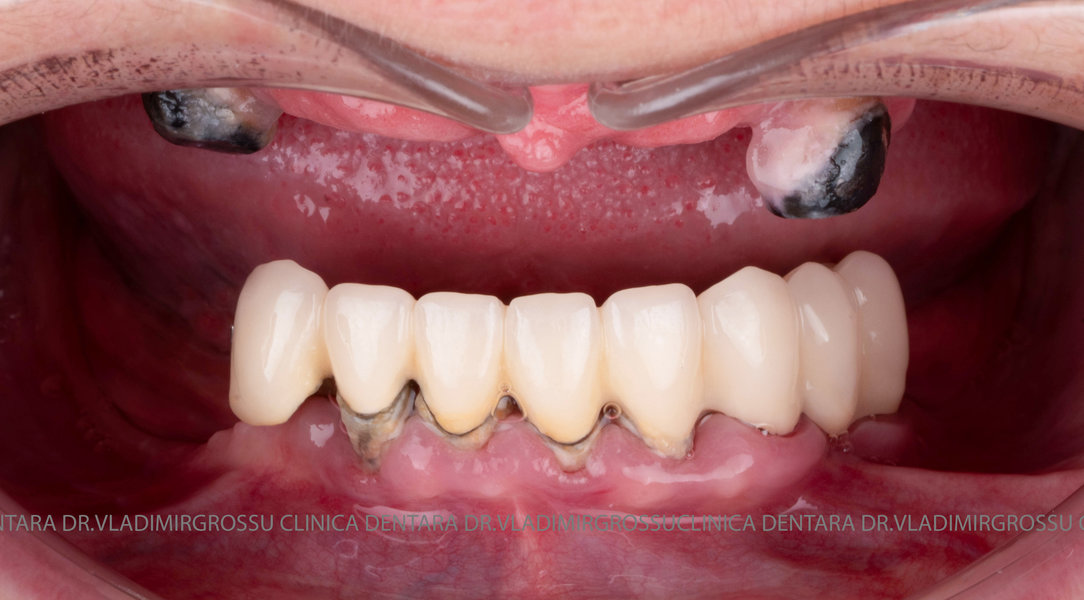

Pentru proteza definitivă:

- 4 abutment-uri permanente pe multiunit-uri;

- Proteză definitivă din metaloceramică sau zirconiu pe o structură metalică, cu 12 unități (soluția recomandată).